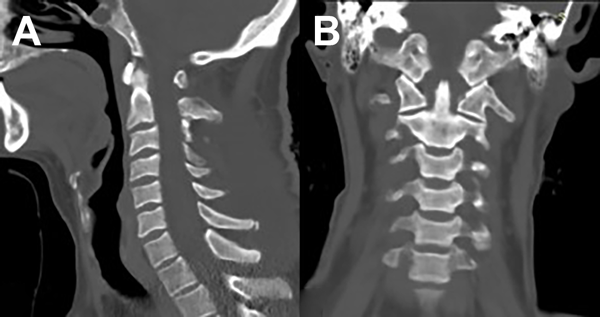

Se comprueba el grado de resección tumoral con RM de columna cervical confirmando la exéresis total macroscópica. Además, se realiza TC de columna cervical de control (Figuras 8 y 9).

Figura 9. TC de columna cervical. A) Corte sagital. B) Corte coronal.